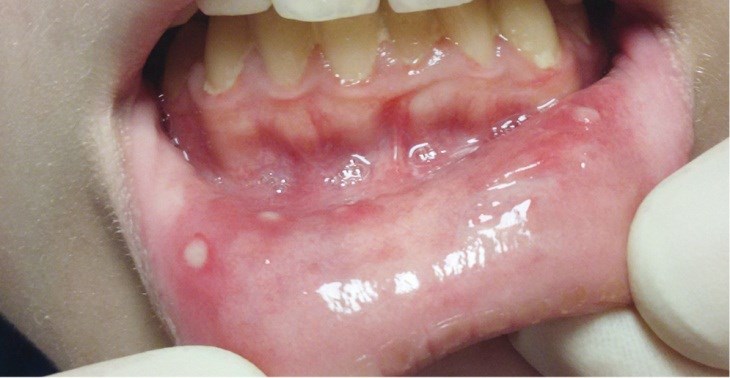

Афтозный стоматит - язвы располагаются на слизистой оболочки губ и щёк. Этот признак проявляется примерно у 40-80% пациентов.